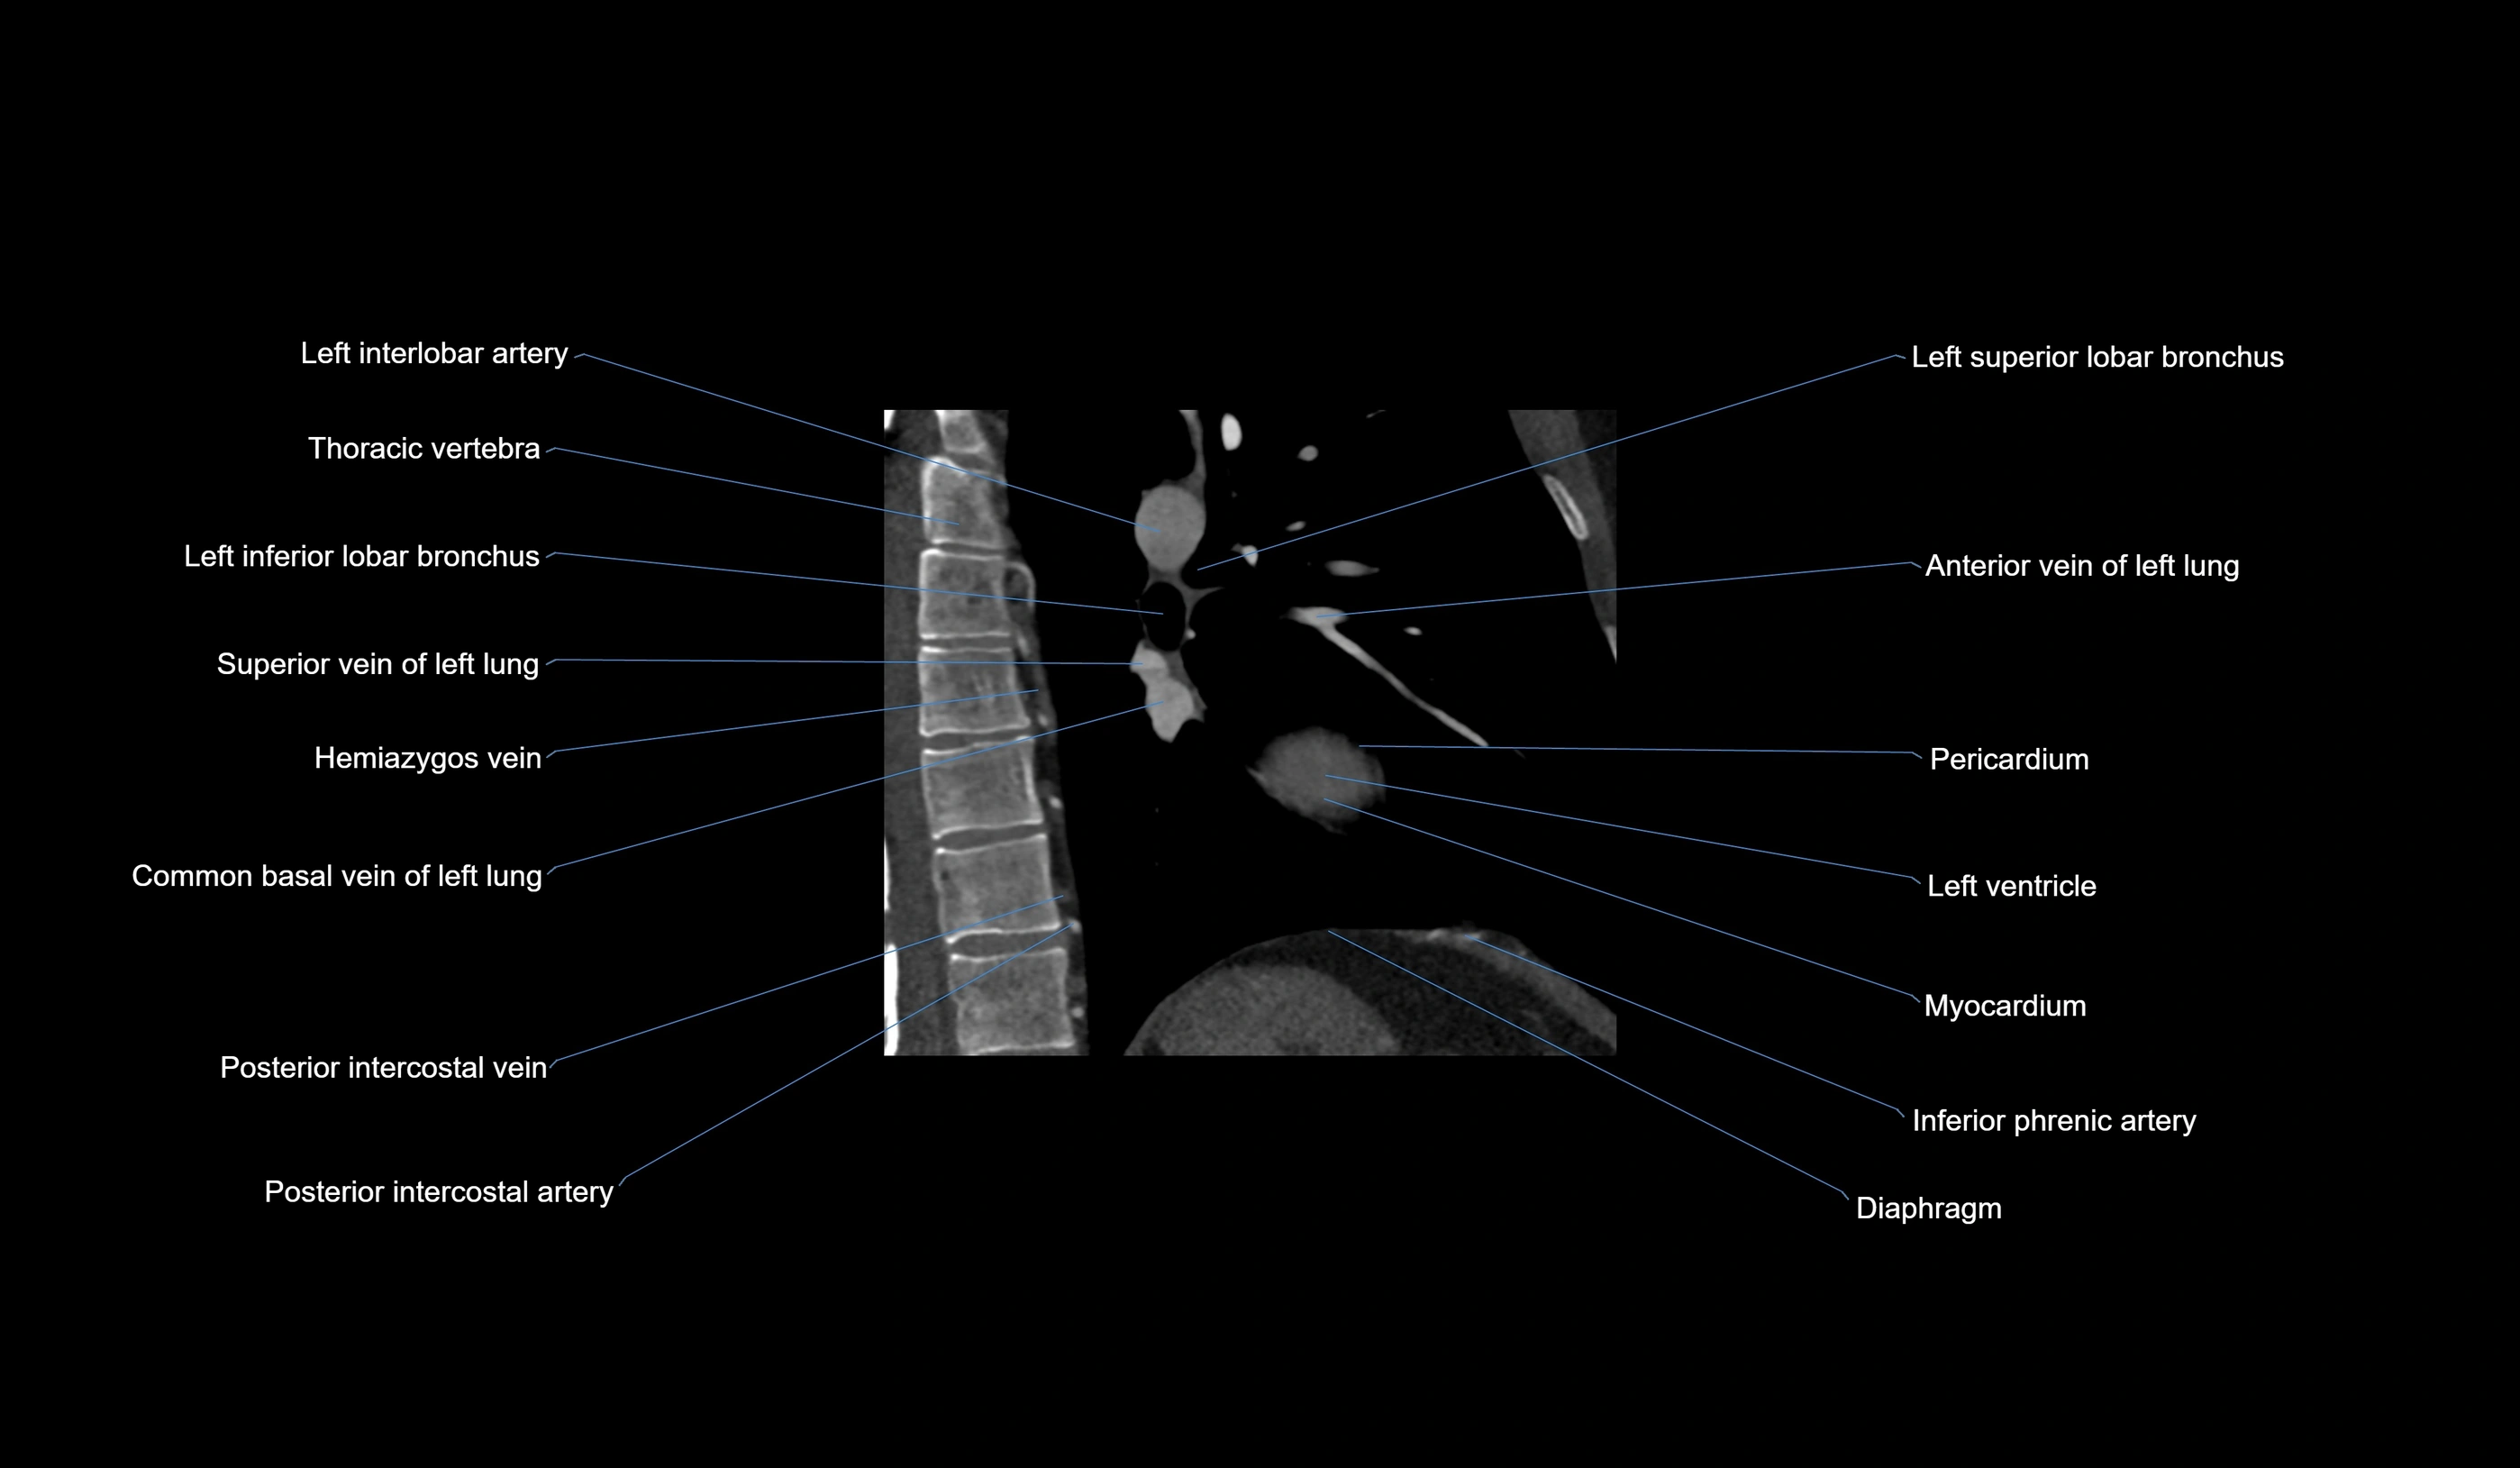

- Left interlobar artery

- Left inferior lobar bronchus

- Left superior lobar bronchus

- Superior vein of left lung

- Anterior vein of left lung

- Pericardium

- Left ventricle

- Myocardium

- Inferior phrenic artery

- Diaphragm